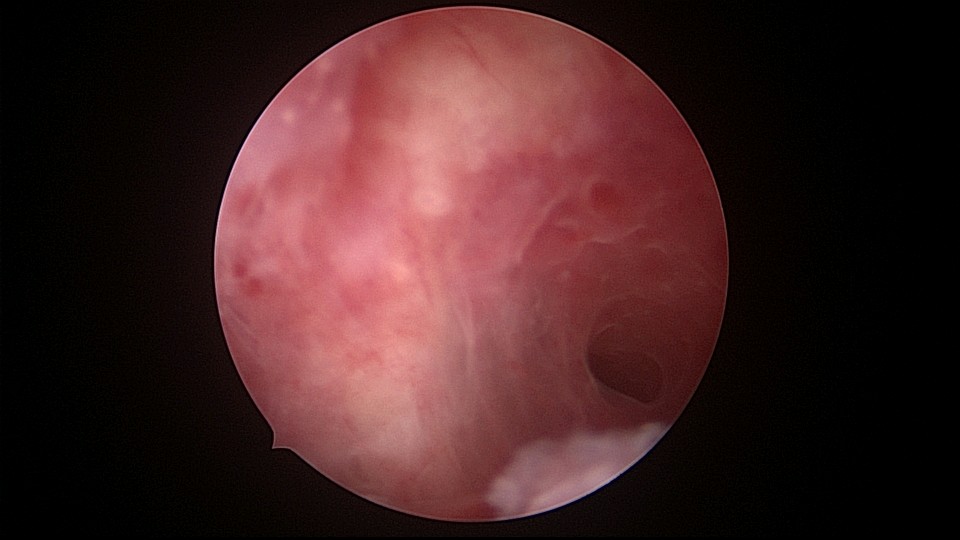

患者34岁,G4P1,顺产1次,继发不孕,宫腔容积小,宫腔粘连。2020年9月宫腔镜探查,见宫腔下段幕状粘连,两侧小孔与宫腔上段相通,形成假的输卵管开口。双极电针切开粘连,宫腔形态恢复正常,显露双侧输卵管正常开口。2020年10月宫腔镜二探取球囊,宫腔形态正常,双侧输卵管开口可见。2021年6月自然妊娠,2022年2月足月剖宫产分娩,2023年5月再次妊娠1次,人流终止妊娠。现39岁,G6P2,顺产1次,剖宫产1次。